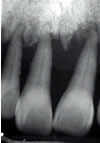

![]() |

|

| 健康な骨 | 破壊した骨 |